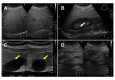

The overall goal in the treatment of type 2 diabetes mellitus (T2DM) is remission. However, the effects of a sodium-glucose cotransporter 2 inhibitor (SGLT2i) on remission of T2DM are unknown. We herein report a case involving an overweight 43-year-old man who completely recovered from T2DM after SGLT2i therapy (dapagliflozin at 5 mg/day). In the pretreatment period, he had a body mass index (BMI) of 26.0 kg/m2, hemoglobin A1c (HbA1c) concentration of 10.3%, advanced insulin resistance, pancreatic β-cell dysfunction, and fatty liver. Eighteen months after comprehensive therapy, including the administration of an SGLT2i and metformin, his BMI had decreased to 21.3 kg/m2 and his glycemic control was almost normal (HbA1c of 5.3%) despite discontinuation of all hypoglycemic medications. This report is the first to propose the usefulness of the combination therapy of SGLT2i and metformin for achieving normal body weight and remission of newly diagnosed T2DM in a real-world clinical situation.